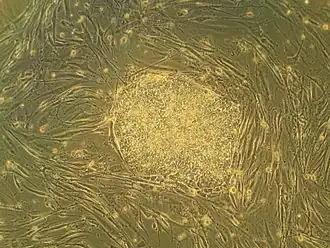

Zarodkowe komórki macierzyste, embrionalne komórki macierzyste, pierwotne komórki zarodkowe – komórki mogące dać początek każdej tkance. Komórki macierzyste pięciodniowego zarodka mogą rozwinąć się w dowolny typ komórek i zastąpić te uszkodzone, których organizm nie jest w stanie odtworzyć.

Komórki macierzyste do tego celu można uzyskać z krwi pępowinowej lub z wyhodowanych zarodków zwierząt lub ludzi. Już teraz komórki macierzyste są wykorzystywane do leczenia choroby Parkinsona, cukrzycy i urazów kręgosłupa u myszy. W organizmie myszy, której wszczepiono komórki macierzyste, uzyskano komórki oka, nerwów, kości i mięśni.